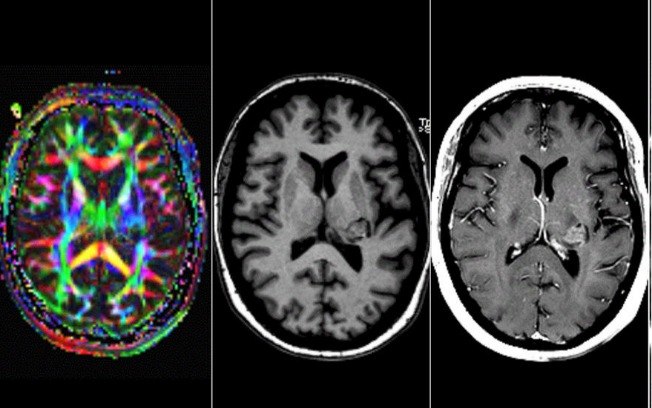

As primeiras suspeitas apontavam para uma doença psiquiátrica, como a esquizofrenia. Contudo, alguns dos sintomas descritos pela paciente instigaram os médicos a pesquisarem um pouco mais a fundo sobre a sua possível condição, o que a levou a fazer uma ressonância magnética cerebral.

O exame revelou uma massa tumoral na estrutura chamada tálamo. “A massa estava localizada em uma rede considerada vital para percepções vocais”, explicou Sebastian Walther, professor de neurociência psiquiátrica , o que justifica as experiências sentidas pela paciente.